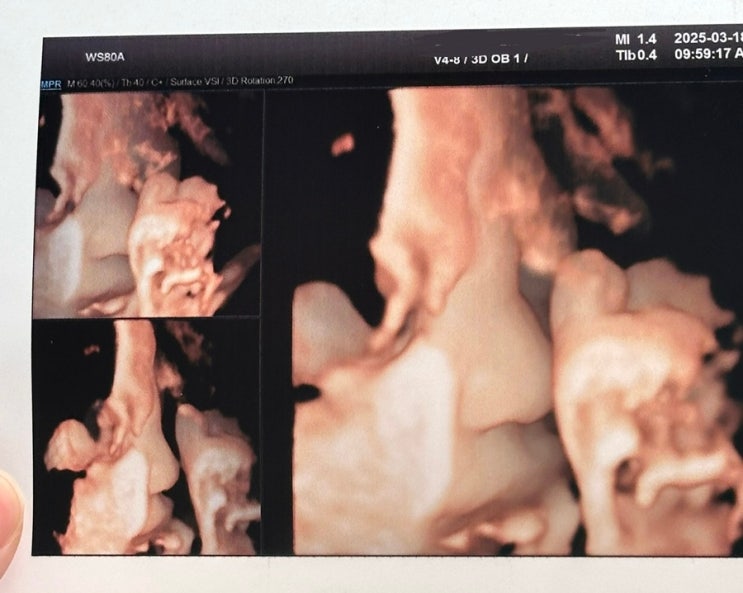

두근두근 드디어 39주 원래 39주 25.04.15인데 어플 날짜가 이상하네 드디어 만복쓰 만나는 날! 이상해 이...

[임신일기] 임신38주차 임신 증상 공유 (최종 출산가방/하이디라오 임산부 혜택/최종푸드)

48.6cm 밀짚모자 만복 와 일주일 남았다… 말도 안돼 진짜로 남은 일주일 그 누구보다 알차게 보내보겠음,,...

[임신일기] 임신37주차 임신 증상 공유

37주 만복이 47.4cm 진짜 이제 몇주 안남았다….. 진료 받으러 갈때마다 아프면 언제든지 병원 오라며.. 방...

[임신일기] 임신36주차 임신 증상 공유 (빨래공장/피아노학원태교)

무 크기가 된 만복.. 46.2cm 태동이 전처럼 활발하지는 않지만 한번 태동 있을때 묵직함 그래도 다른 태아...

[임신일기] 임신35주차 임신 증상 공유 (만삭사진/하이디라오 임산부 혜택/신생아빨래공장 베베룬 손수건)

35주차 만복이 옷걸이만한 45cm 이제는 가늠도 안됨,, 이만한게 내 뱃속에 있다고!!? 만복이는,, 오늘도 건...

[임신일기] 임신33주차 임신 증상 공유 (아난티앳강남 호캉스)

파인애플 만복이 42.4cm 피하지방이 늘어나고 주름이 없어짐 피부색은 피하지방이 늘어나 붉은 기운이 옅어...

[임신일기] 임신34주차 임신 증상 공유 (플라워샵온스 원데이클래스, 그랜드 워커힐 호텔 호캉스)

양푼비빔밥 만복이 43cm!!!!! 이제 머리가 아래로 향해서 분만위치를 잡아둠!! 감각기관이 꽤 발달해서 자...

[임신일기] 임신31주차 임신 증상 공유

헌터부츠 만복쓰 39.3cm 이제는 지금 당장 태어나도 인큐베이터의 도움으로 생존도 가능하다는.. 몸에 살은...